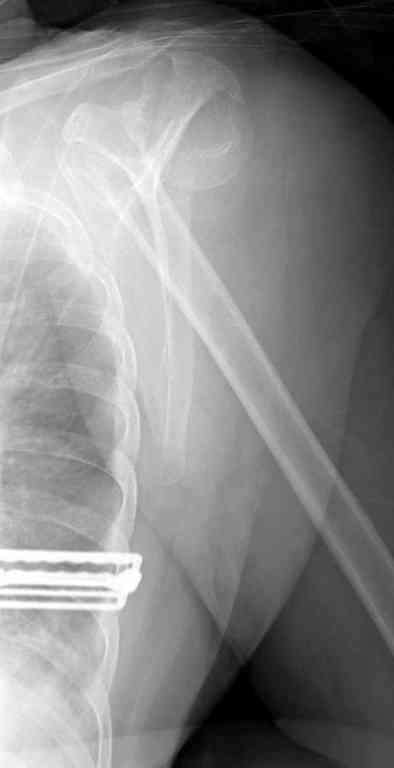

> Боковой снимок нормально не сделать, вторая проекция сделана под углом 30 градусов.

Вполне нормальный и читаемый снимок - лопаточная или Y проекция входит в "травма-серию" плечевого сустава как стандарт.

Относительно контрольного КТ - впечатление такое, что малость перестарались при репозиции.

Оставлять такой диастаз пожалуй нежелательно. Мы бы вправляли закрыто и фиксирoвали спицами через головку в диафиз - в большинстве случаев получалось неплохо, тем более - перелом вроде двухфрагментарный. ЭОП-контроль на столе - если что-то не так - ORIF.